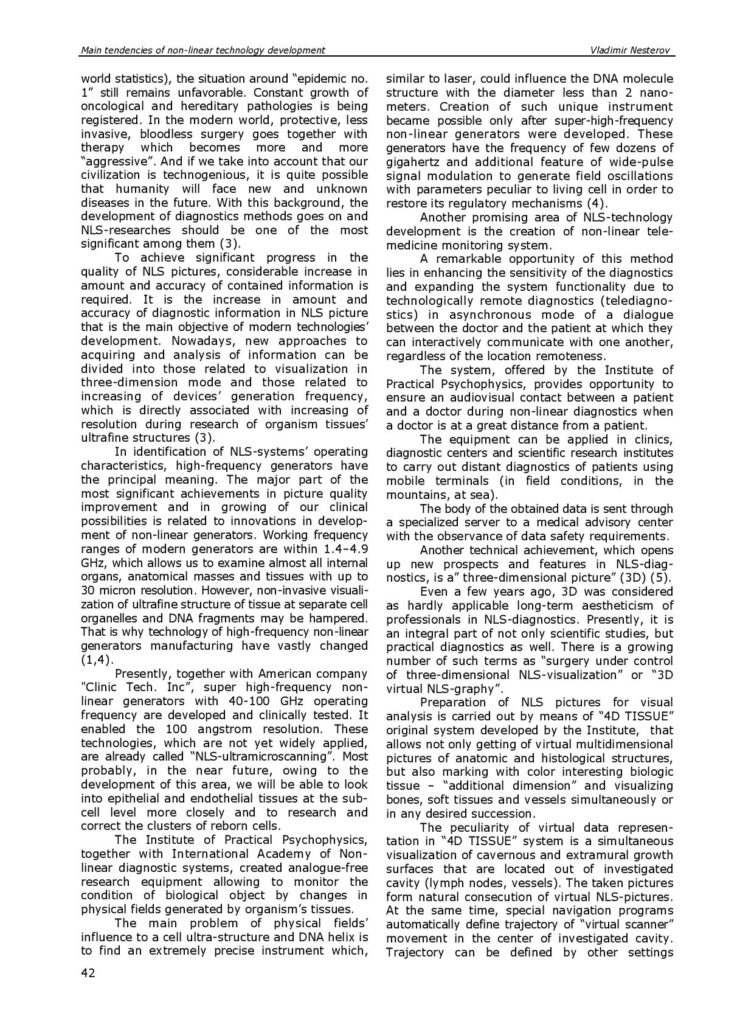

NLS - diagnostyka urazów mięśni u sportowców